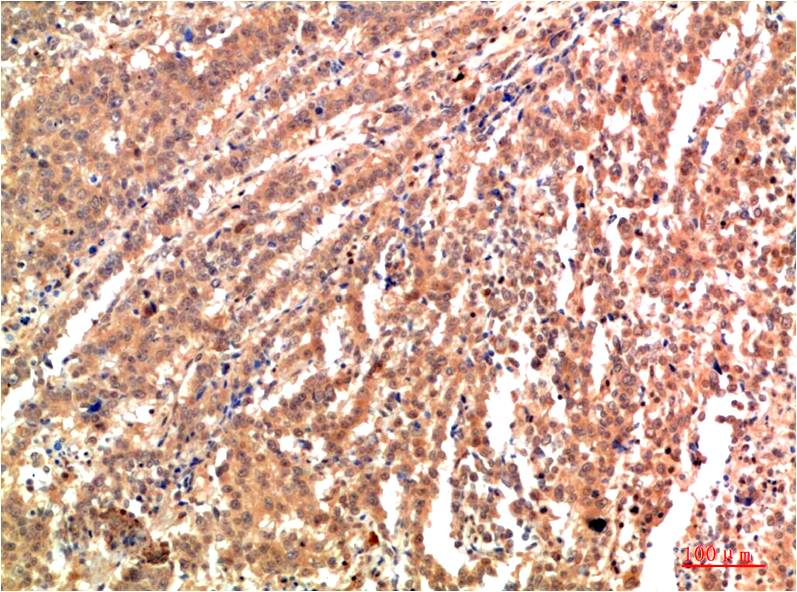

| Dilutions: | WB 1:500-1,000 IHC 1:100-200 |

| Cellular localization: | Cytoplasm, Nucleus |